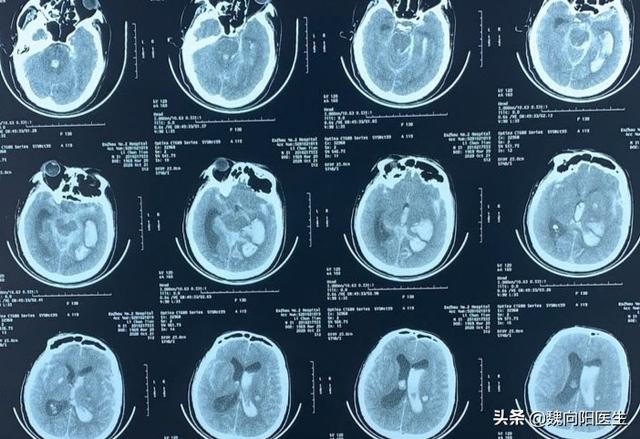

脳出血は神経内科領域における主要な救急疾患であり、急性発症、高障害率、高死亡率を示し、患者の家族や社会全体に非常に深刻な経済的負担をもたらす。

脳にとって最も重要な危険因子は高血圧で、脳出血のおよそ95%に関与している。特に高血圧が若年化している現在、脳出血を発症する若者が増えている。

脳出血の徴候

- 急激な血圧上昇を伴う頭痛、著しい頭部の腫脹、吐き気や嘔吐を伴う頭痛は、脳出血の可能性と同様に疑われるべきである。

くも膜下出血の最も顕著な症状は、首のこわばりを伴う激しい頭痛である。

- 片方の手足の突然の好ましくない動き、体の片側の感覚障害、好ましくない話し方、口が曲がる。

- 両眼の片側の突然の注視、両眼の片側の視野欠損、複視など。

- 突然の昏睡!